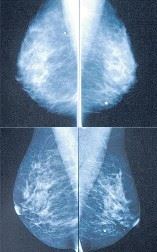

5. De technologe maakt de beelden (2 per borst).